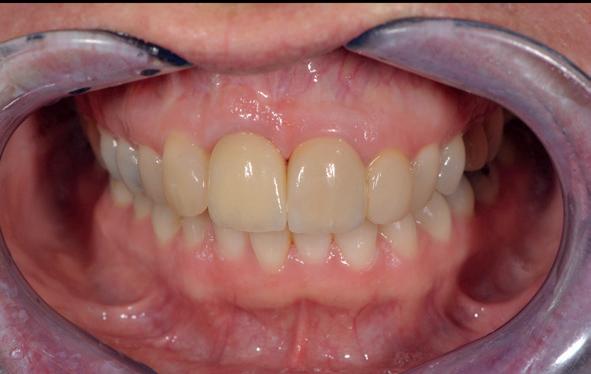

13. Techniekmodel

plaatsing van de restauraties werden zowel de tandboog als de tandstand in de bovenkaak gecorrigeerd (afbeelding 13-15).

Aansluitend werd de onderkaak volgens hetzelfde principe gerehabiliteerd, resulterend in een stabiele, functionele en esthetisch gebalanceerde occlusie (afbeelding 16-17).